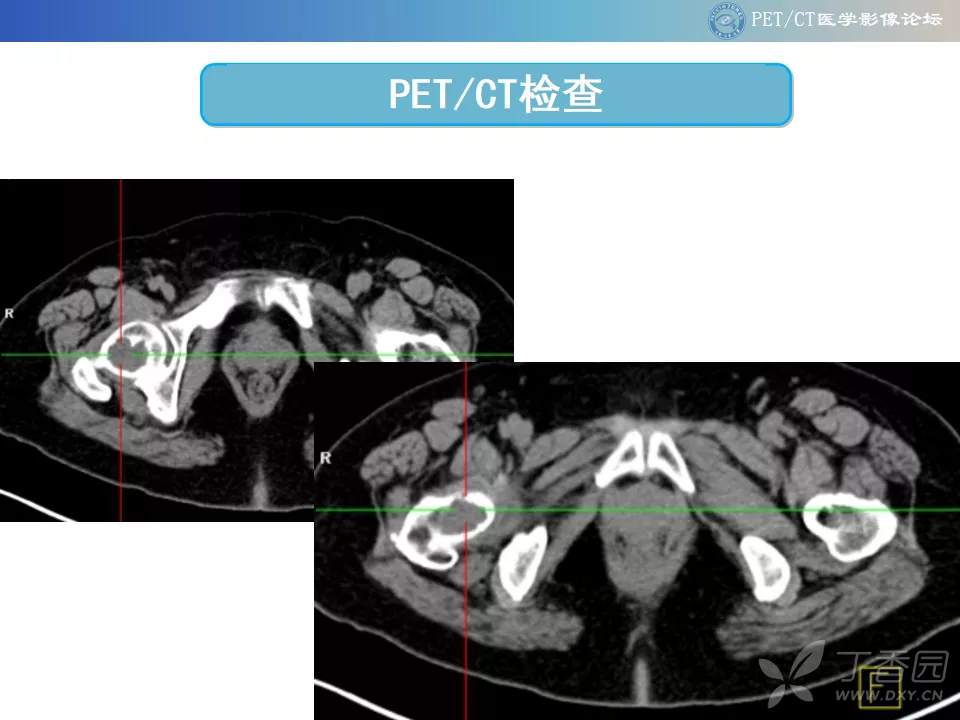

【PET/CT 病例读片】髋关节占位性病变

注:病例来源【PETCT病例读片第二十二期】

查看病例结果及诊断分析请关注公众号【PETCT医学影像论坛】